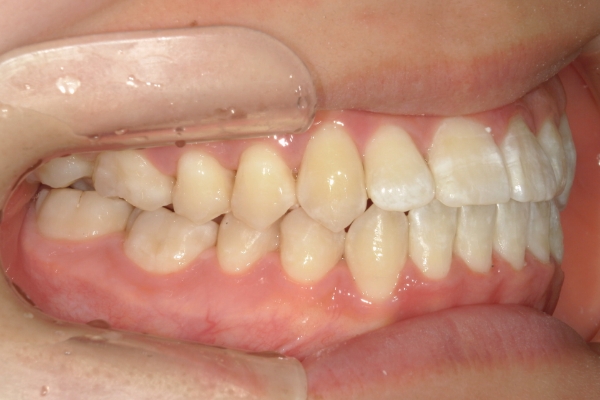

BEFORE

治療前

PROCESS

3か月

AFTER

治療後

骨格的に下あごが前下方に長いことが原因で、受け口、開咬(前歯が当たらない)の症状がでていました。また下あごが右にずれており、その影響で上下の歯列正中(真ん中)の大きなずれも生じていました。顎変形症手術も選択肢の一つでしたが、患者さまの希望もあり、下顎左側小臼歯の抜歯をして通常の歯列矯正で治療をしました。

治療後は、前歯、奥歯の噛み合わせが整い、上下の歯列の真ん中が一致しました。歯列全体のアーチも安定し、機能面・審美面のどちらも大きく改善されました。